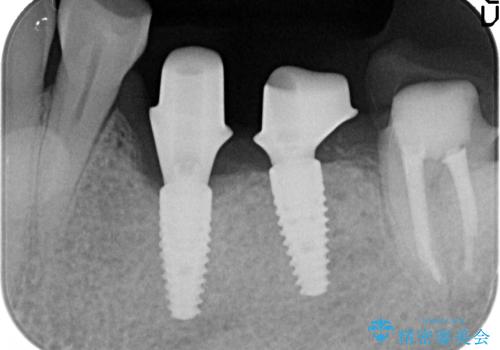

- 左下奥歯が虫歯で抜歯になってしまったため、インプラントにしたいといらっしゃった方の症例です。

欠損部位である左下5、6番目にインプラントを埋入し、オールセラミッククラウンによる補綴を行いました。

左下7番目は再根管治療を行い、オールセラミッククラウンによる補綴を行いました。